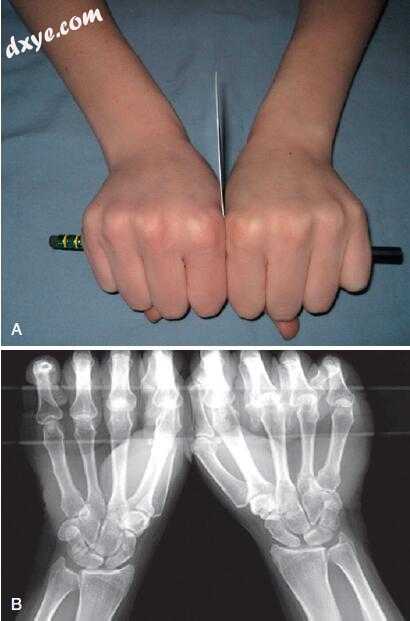

8.jpg

图.8  紧握铅笔的视力。受试者在握住一根铅笔时,轻轻地在第一个骨间背肌之间按压一张卡片。B、后前片呈现出非对称的舟月扩大。 (A and B, From Lee SK, Desai H, Silver B, et al: Comparison of radiographic stress views for scapholunate dynamic instability in a cadaver model. J Hand Surg [Am] 36:1149– 1157, 2011.)